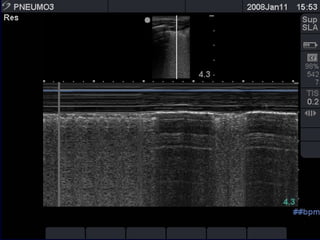

the "seashore sign" (Fig.3).

Absent lung sliding

Exaggerated horizontal artifacts

Loss of comet-tail artifacts

Broadening of the pleural line to a band

The key sonographic signs of

Pneumothorax

Absent lung sliding Exaggeratedhorizontal artifacts Loss of comet-tail artifacts Broadening of the pleural line to a band The key sonographic signs of Pneumothorax